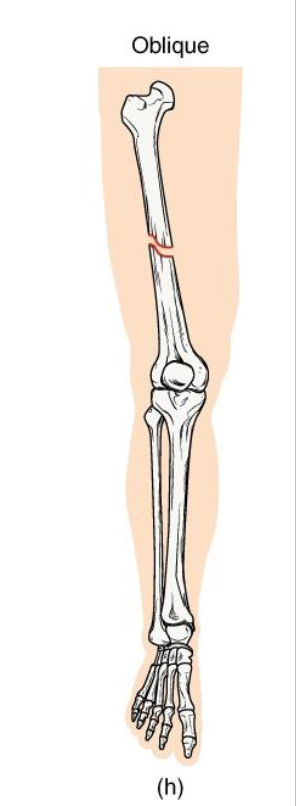

Oblique Fracture

Definition: Diagonal fracture line across the bone shaft.

Mechanism: angles force applied along the long axis.

Clinical note: Sharp ends may lead to displacement; requires stabilization.

Key concept: often confused with spiral fractures - but lacks twist pattern

<p><strong>Definition: Diagonal fracture line</strong> across the bone shaft.</p><p><strong>Mechanism</strong>:<strong> angles force applied along the long axis.</strong></p><p><strong>Clinical note:</strong> Sharp ends may lead to displacement; requires stabilization.</p><p><strong>Key concept: often confused with spiral fractures -</strong> but lacks twist pattern</p>